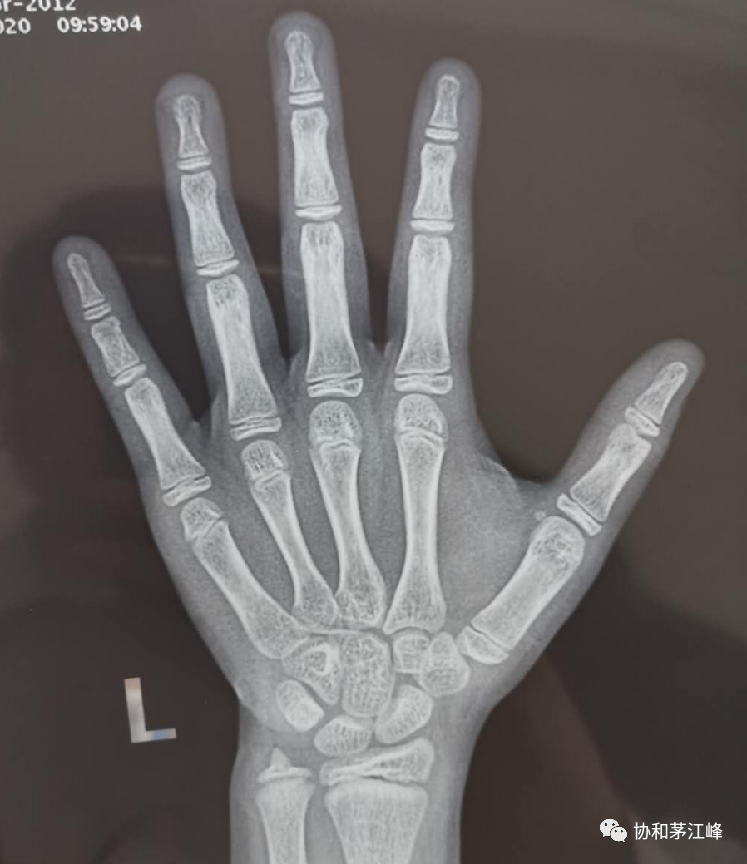

从基本情况来看,孩子到医院后,首先需对左手腕掌指进行X线照片,以了解骨龄,判断孩子骨骼生长情况,骨骺发育的程度和生长潜力。其次还要做血、尿常规、血肝肾功能、血钙、磷和碱性磷酸酶,第三要进行生长激素相关检查(先查甲状腺素、生长因子水平等)。女孩子还要查血染色体核型以确定是否为“先天性卵巢发育不全综合症”。

(骨龄11岁,有图有真相)